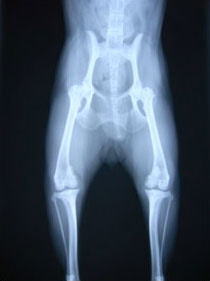

膝蓋骨が大腿骨遠位の滑車溝から内方または外方に転移する状態

内方膝蓋骨脱臼の発生原因は内反股と大腿骨頸の前捻であると結論づけている研究があります。また、遺伝的要素が重要と考えられており、大腿四頭筋機構の異常、股関節異常、後肢の変形との関連などが報告されておりますが、現在でも正確な病因あるいは発生機序は分っておらず、治療方針や合併症の問題に関して議論が続いています。10kg以下の小型犬に多く認められる傾向があること、大型犬でも内方への脱臼が全体の75~90%を占める傾向があります。